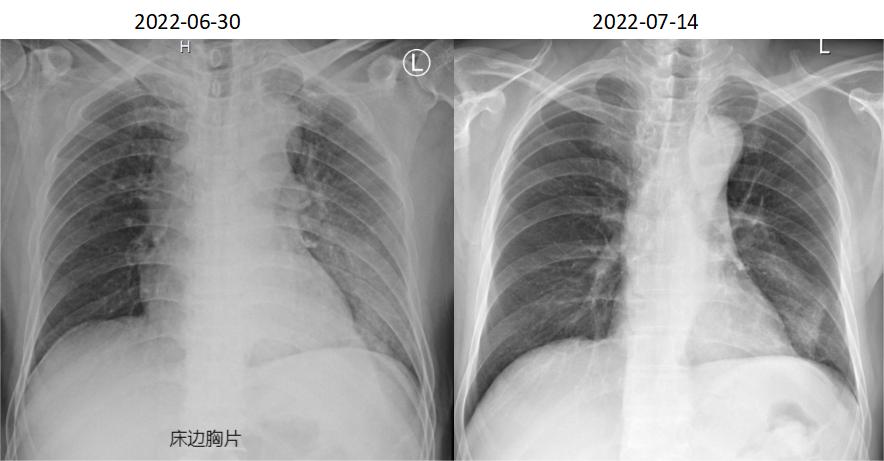

患者6.29、6.30仍反复高热,热峰39℃以上,复查感染指标PCT及CRP下降,但临床症状改善不显著,仍反复高热。 气促症状无好转,查床边胸片提示病灶范围较前明显增加。 追问病史, 患者曾在地下车库扫水 ,入院前至今反复有腹泻、解稀烂便或水样便3-4次/日。

该患者的另一个临床特征是高PCT水平,据文献报道高PCT水平与需ICU治疗和高死亡率相关。 我们注意到,在病程中,PCT水平与体温未成平行下降关系,可能的原因为: 患者在入院初存在胃肠道症状和体征,包括腹泻、肠鸣音亢进。肠道作为细菌的蓄水池,此类患者可能存在肠道菌群移位。虽然没有相应的文献支持,我们在明确病原体为军团菌后,仍然将美平保留到7月2日,与多西环素重叠使用3天,直至PCT下降到安全范围。尽管在多西环素介入后, 6月30日床边胸片提示病灶较前明显增多,左肺大片浸润影,考虑到患者重症肺炎以及多个死亡相关预后因素存在,加用利福平5天联合抗军团菌。 患者在有效抗感染治疗基础上,7月6日复查胸部CT提示机化表现 ,氧合改善欠佳,给予短程激素应用,7月14日复查胸片提示病灶显著吸收。1个月后电话随访,患者原有咳嗽、气促等症状消失。